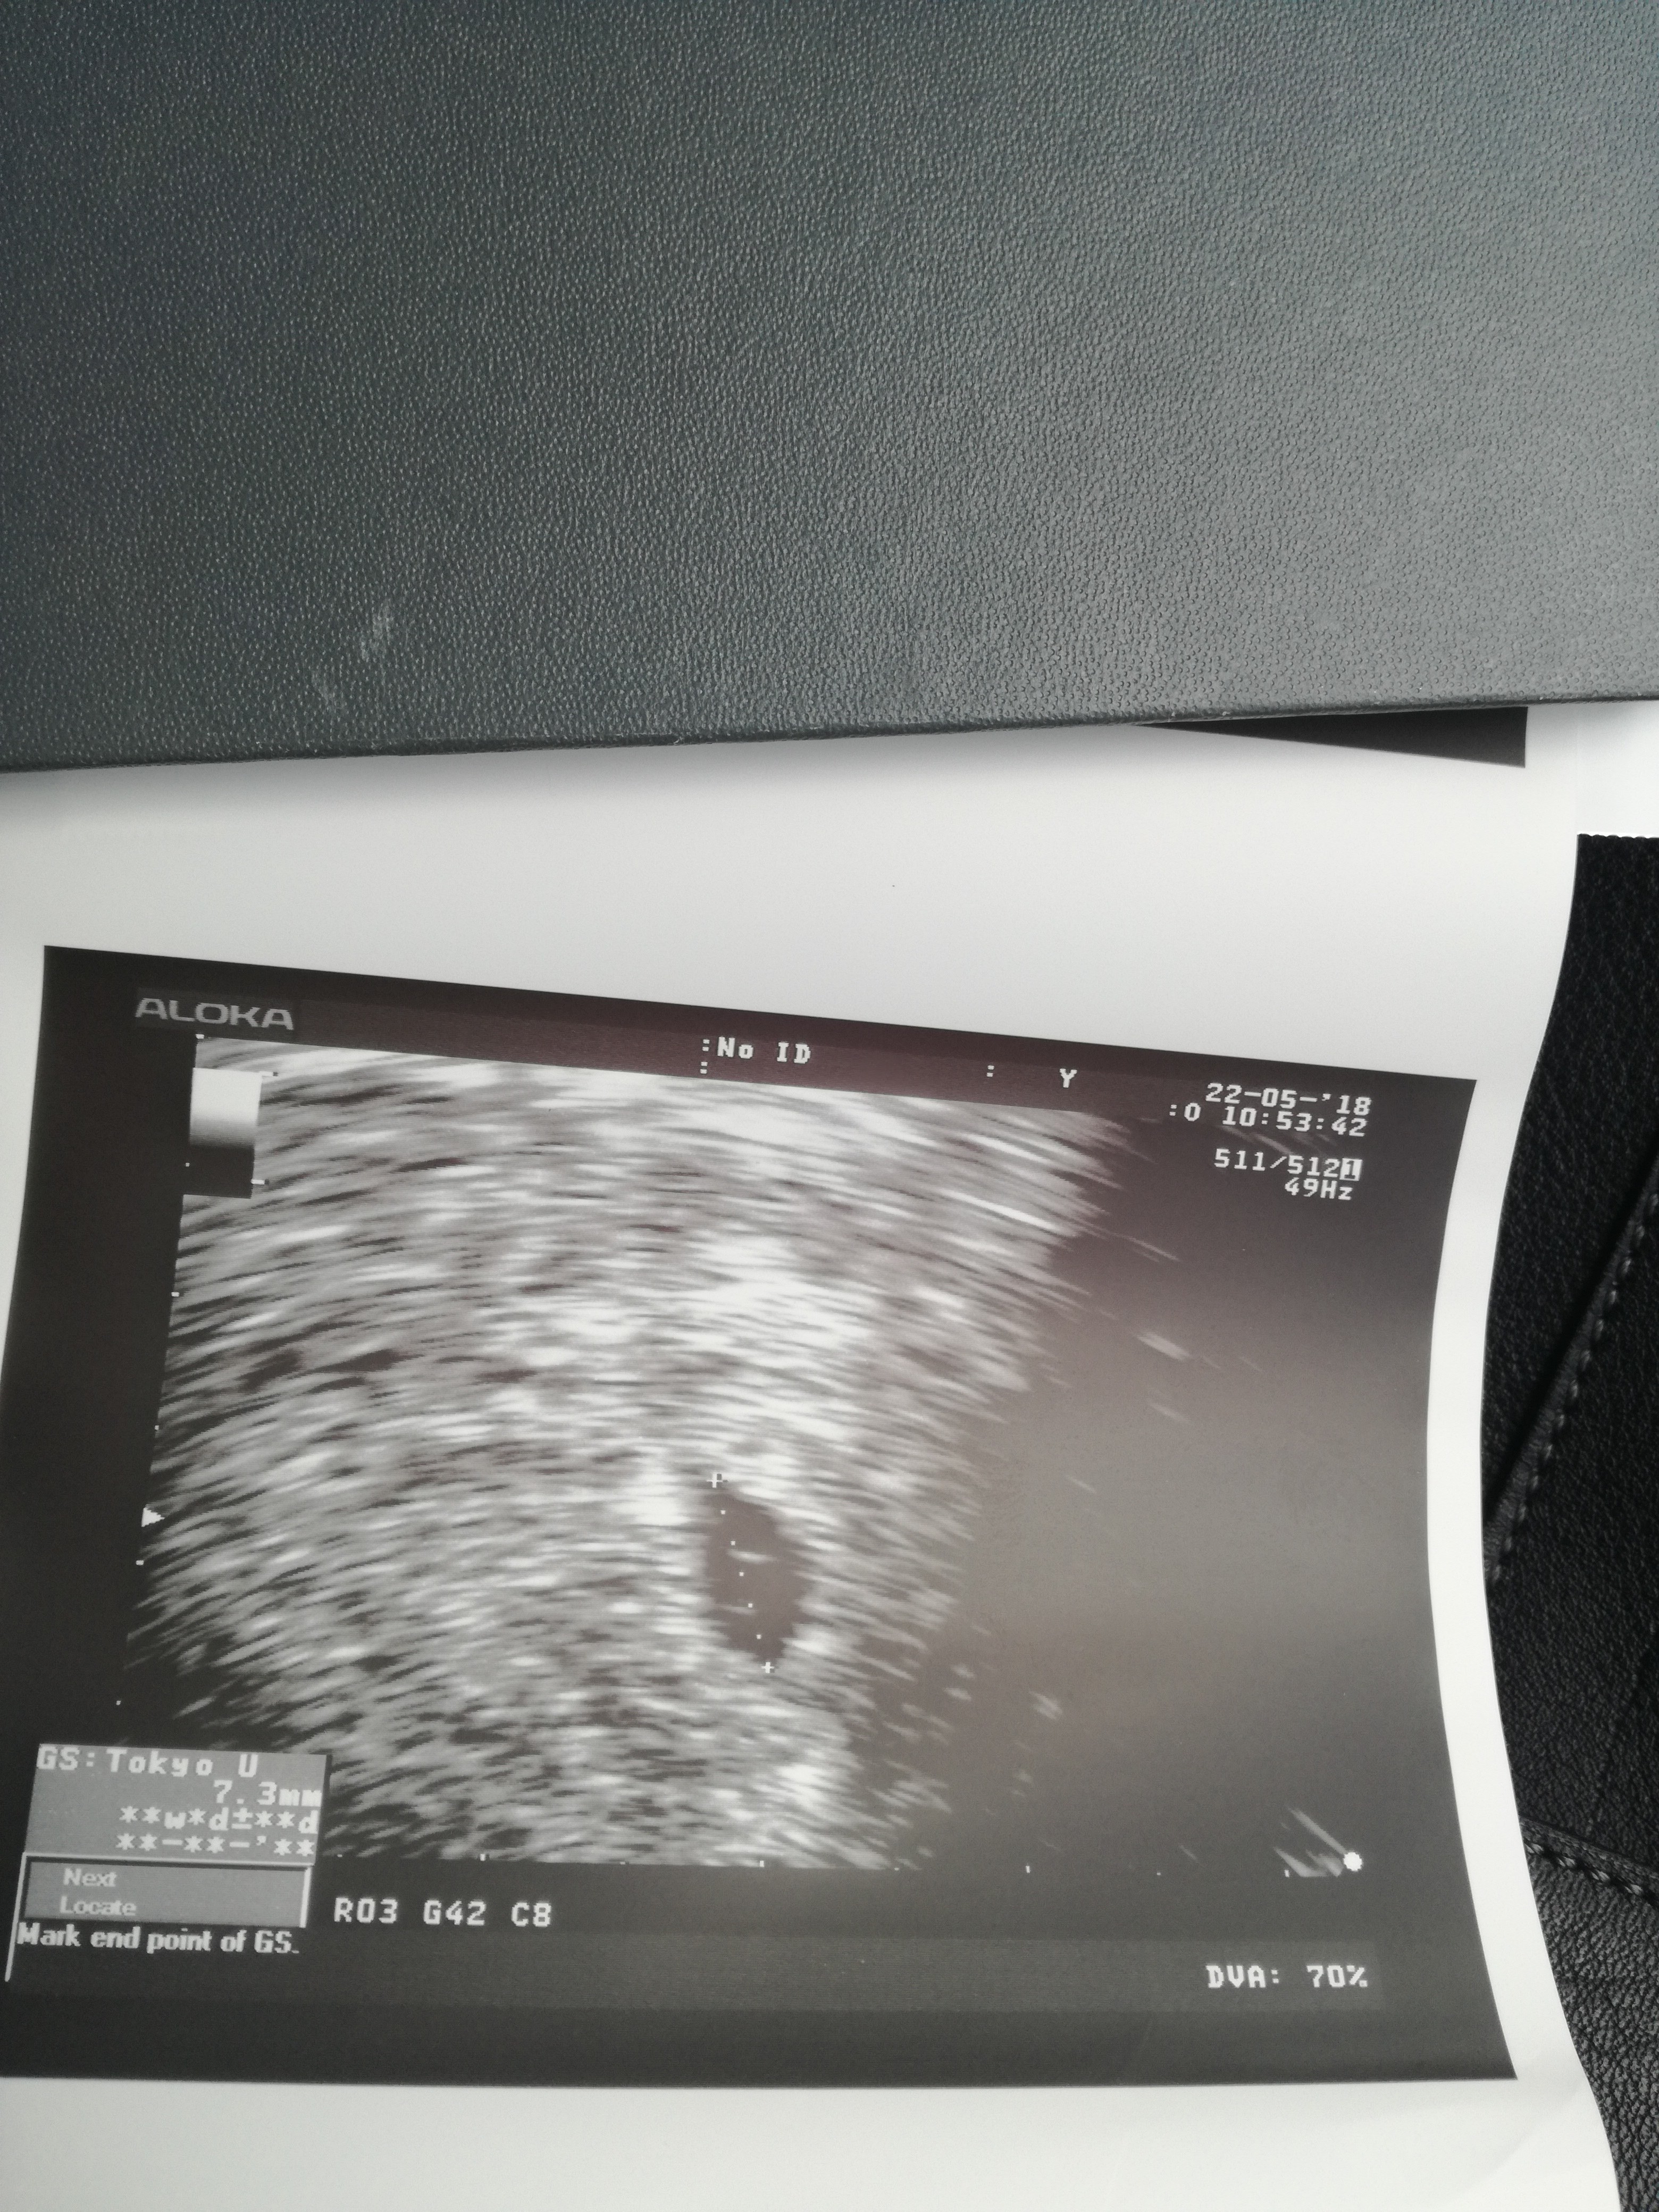

Co za wspanialy widok!!!!! [emoji173][emoji173][emoji173][emoji173]Dziewczynki jestem pi wizycie pecherzykowej 17dpt blastki. Czyli 5+1 niby.

Jest jeden pecherzyj z cialkiem żółtym, 7,3mm